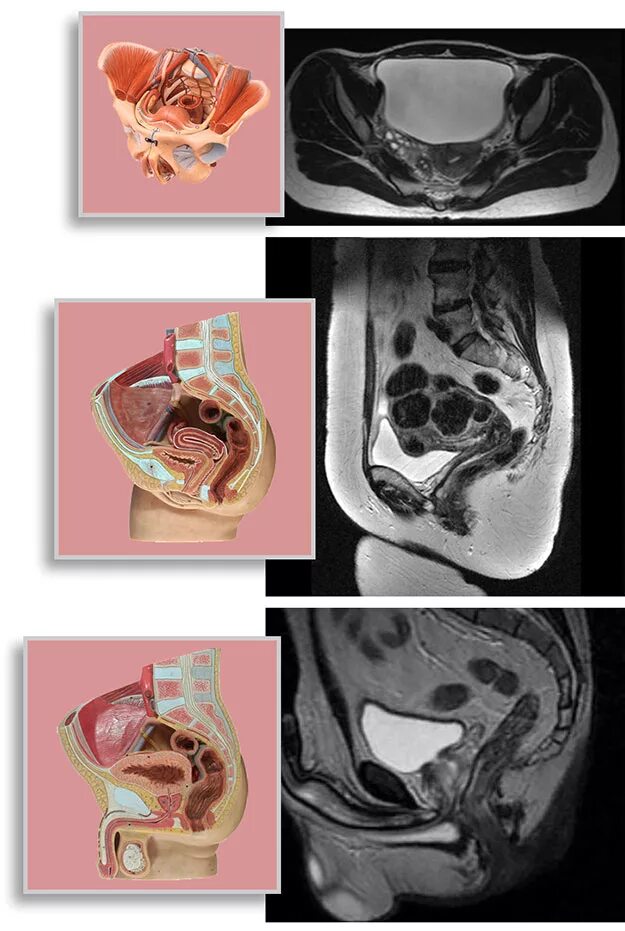

Где можно сделать кт малого таза